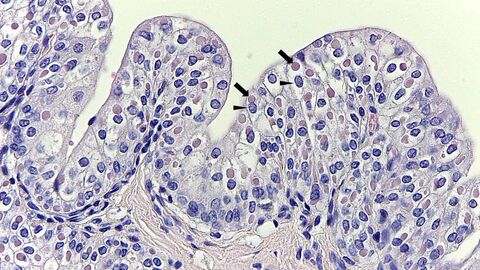

Bei toten Tieren gibt die Obduktion näheren Aufschluss über die Erkrankung. Durch die feingewebliche (histologische) Untersuchung lässt sich eine Staupeerkrankung mit gewisser Sicherheit – durch den Nachweis von Einschlusskörperchen in Virus-infizierten Zellen (siehe Abbildung 1) - diagnostizieren. Der sicherste Nachweis gelingt mittels real-time RT-PCR aus Organmaterial.

Eosinophile intrazytoplasmatische Einschlusskörperchen im Übergangsepithel der Harnblase eines Fuchses

Abb. 1: Zahlreiche eosinophile intrazytoplasmatische Einschlusskörperchen (Pfeil) im Übergangsepithel der Harnblase eines Fuchses. Basophile Zellkerne sind mit Pfeilspitzen gekennzeichnet. Präparat aus der Diagnostik des Hessischen Landeslabors.